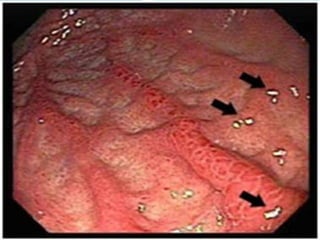

Radang pada Dinding Lambung (Gastritis)

 Radang dinding lambung merupakan peradangan yang terjadi pada

membran mukus yang melapisi lambung. Gejala radang dinding

lambung misalnya kesulitan bernapas, feses hitam bercampur darah,

sakit kepala, dan rasa tidak nyaman di perut bagian atas. Radang

dinding lambung dapat disebabkan terhadap makanan tertentu,

alkohol, obat-obatan (misalnya aspirin), racun (misalnya amonia dan

merkuri), dan bakteri tertentu.

 Radang dinding lambung (tanda panah)

 Pengobatan radang dinding lambung bergantung pada penyebabnya.

Misalnya, radang dinding lambung yang disebabkan racun diobati

dengan anticholinergic seperti methantheline bromide. Radang dinding

lambung yang disebabkan bakteri diobati dengan antibiotik. Radang

dinding lambung dapat dicegah dengan menghindari alkohol, aspirin,

dan membiasakan pola makan yang sehat dan seimbang.